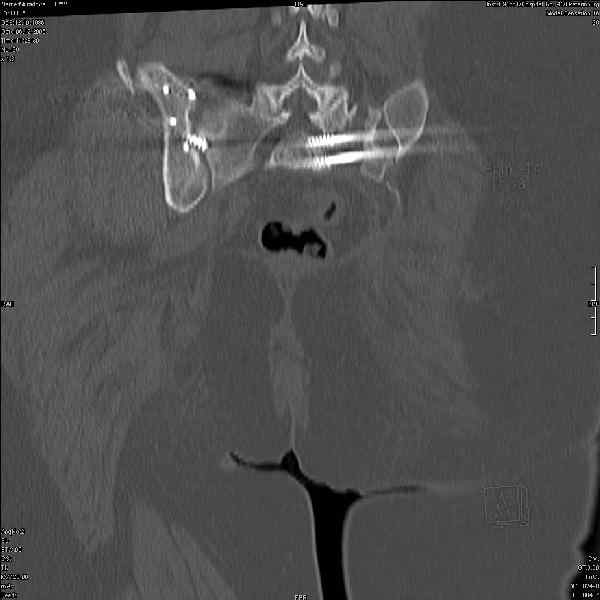

Здравствуйте, коллеги. Какие будут мнения по поводу лечения представляемой больной?

Молодая девушка 19 лет, травма 1 год назад, тогда же прооперирована.

В настоящее время имеются ноющие боли в области крестца слева, нарушение походки, ощущение неуверенности, слабости в левой нижней конечности, неврологически -непостоянные парестезии в левой нижней конечности. Ходит с дополнительной опорой, страдает от ожирения.

В приложении снимки при поступлении и послеоперационные год назад.

Могу сказать одно: миграция винтов и нестабильность синтеза левого подвздошно-крестцовогоо сочленения очевидна.